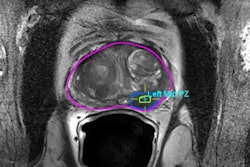

Half of the images were prior exams acquired three years before the onset of visible cancer, and half were benign. The readers rated the likelihood of abnormality on a scale of zero to 100 and categorized breast density. The researchers measured reader performance using area under the curve (AUC) analysis.

The team found that in all three groups, readers could identify abnormal images on the mammograms taken three years prior to visible signs of breast cancer (p < 0.001). These results were not influenced by breast density.